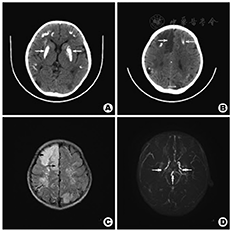

患儿,男,5岁,因"发热3 d,精神萎靡伴四肢乏力1 d"于2013年12月20日入院。3 d前开始出现发热,体温最高达38.8 ℃,伴寒战,无抽搐,有咳嗽,无气喘,无呕吐及腹泻。起病后输液3次(头孢等)热退,入院当天家属诉患儿精神萎靡,不愿言语,表情淡漠,且伴四肢明显无力,冰凉,不能站立。既往史及家族史:出生时正常。家族无遗传、代谢病史,也无类似的疾病史。患儿近1年来经常诉头晕,未检查治疗。入院体格检查:精神萎靡,表情淡漠,问之不答,颈软,双肺及心脏听诊正常,腹平软,肝脾未及,左上肢及左下肢肌力Ⅱ级,右上肢及右下肢肌力Ⅳ级,其余体检均正常。入院初步诊断:中枢神经系统感染?入院后头颅CT提示"双侧大脑半球皮质可见多发性斑片状钙化影,呈对称分布,双侧额叶、右枕叶及左顶叶可见片状低密度灶,边界欠清,部分囊性变"(图1A, 图1B)。诊断:⑴双侧大脑半球多发性高密度钙化灶,考虑为代谢性疾病"Fahr综合征"(特发性非家族性基底节钙化综合征)。⑵双侧大脑半球多发性低密度灶,考虑大面积脑梗死。急诊头颅MRI+MRA(磁共振血管成像)显示:双侧顶叶及颞叶,可见片状长T2信号,右侧额叶及左侧枕顶叶脑回肿胀,并可见片状长T2信号,DWI上呈现高信号改变,双侧基底节区及额叶可见斑片状混杂信号灶,双侧颈内动脉虹吸曲C1段狭窄,双侧大脑前、中、后动脉不同程度狭窄,大部分分支未显影,颅内见多发扭曲管影(图1C, 图1D)。诊断:⑴亚急性脑梗死,⑵Moyamoya病(烟雾病),⑶双侧基底节区钙化灶。血常规正常,肝肾功能、心肌酶谱正常,血氨正常,免疫全套正常,病原学检查均为阴性,风湿全套正常,脑脊液常规检查正常;血钙及血磷均正常,其他电解质均正常。甲状腺激素水平均正常。甲状旁腺激素水平2.95 pmol/L(正常值1.5~10 pmol/L)。综合患儿的临床表现及辅检结果,诊断为"Moyamoya病合并Fahr综合征"。入院后给予扩管,脱水,营养神经等处理,患儿精神反应、语言表达逐渐好转,右侧肢体肌力恢复正常,左侧肢体肌力逐渐恢复Ⅳ级。病情稳定后,转北京协和医院神经内科进一步确诊,完善相关检查排除了"线粒体脑肌病"等遗传性疾病,诊断为Moyamoya病合并Fahr综合征。